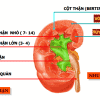

– Cấu tạo thận: xoang thận ở giữa – xung quanh là nhu mô thận (vỏ thận + tủy thận)

+ Xoang thận: chứa mạch máu và thần kinh thận, hệ thống đài bể thận và mô liên kết mỡ. Đài thận nhỏ nhận nước tiểu từ nhú thận, đổ ra đài thận lớn, đài thận lớn hợp thành bể thận – nối với niệu quản.

+ Vỏ thận: nằm ngay dưới bao thận, gồm cột thận (giữa các tháp thận) và các tiểu thùy vỏ từ đáy tháp thận tới bao thận.

+ Tủy thận: do các tháp thận (tháp Malpighi) tạo nên. Đáy tháp thận hướng về phía vỏ thận, đỉnh hướng về phía xoang thận, lồi vào trong xoang thận tạo nên nhú thận – nối với đài thận nhỏ.